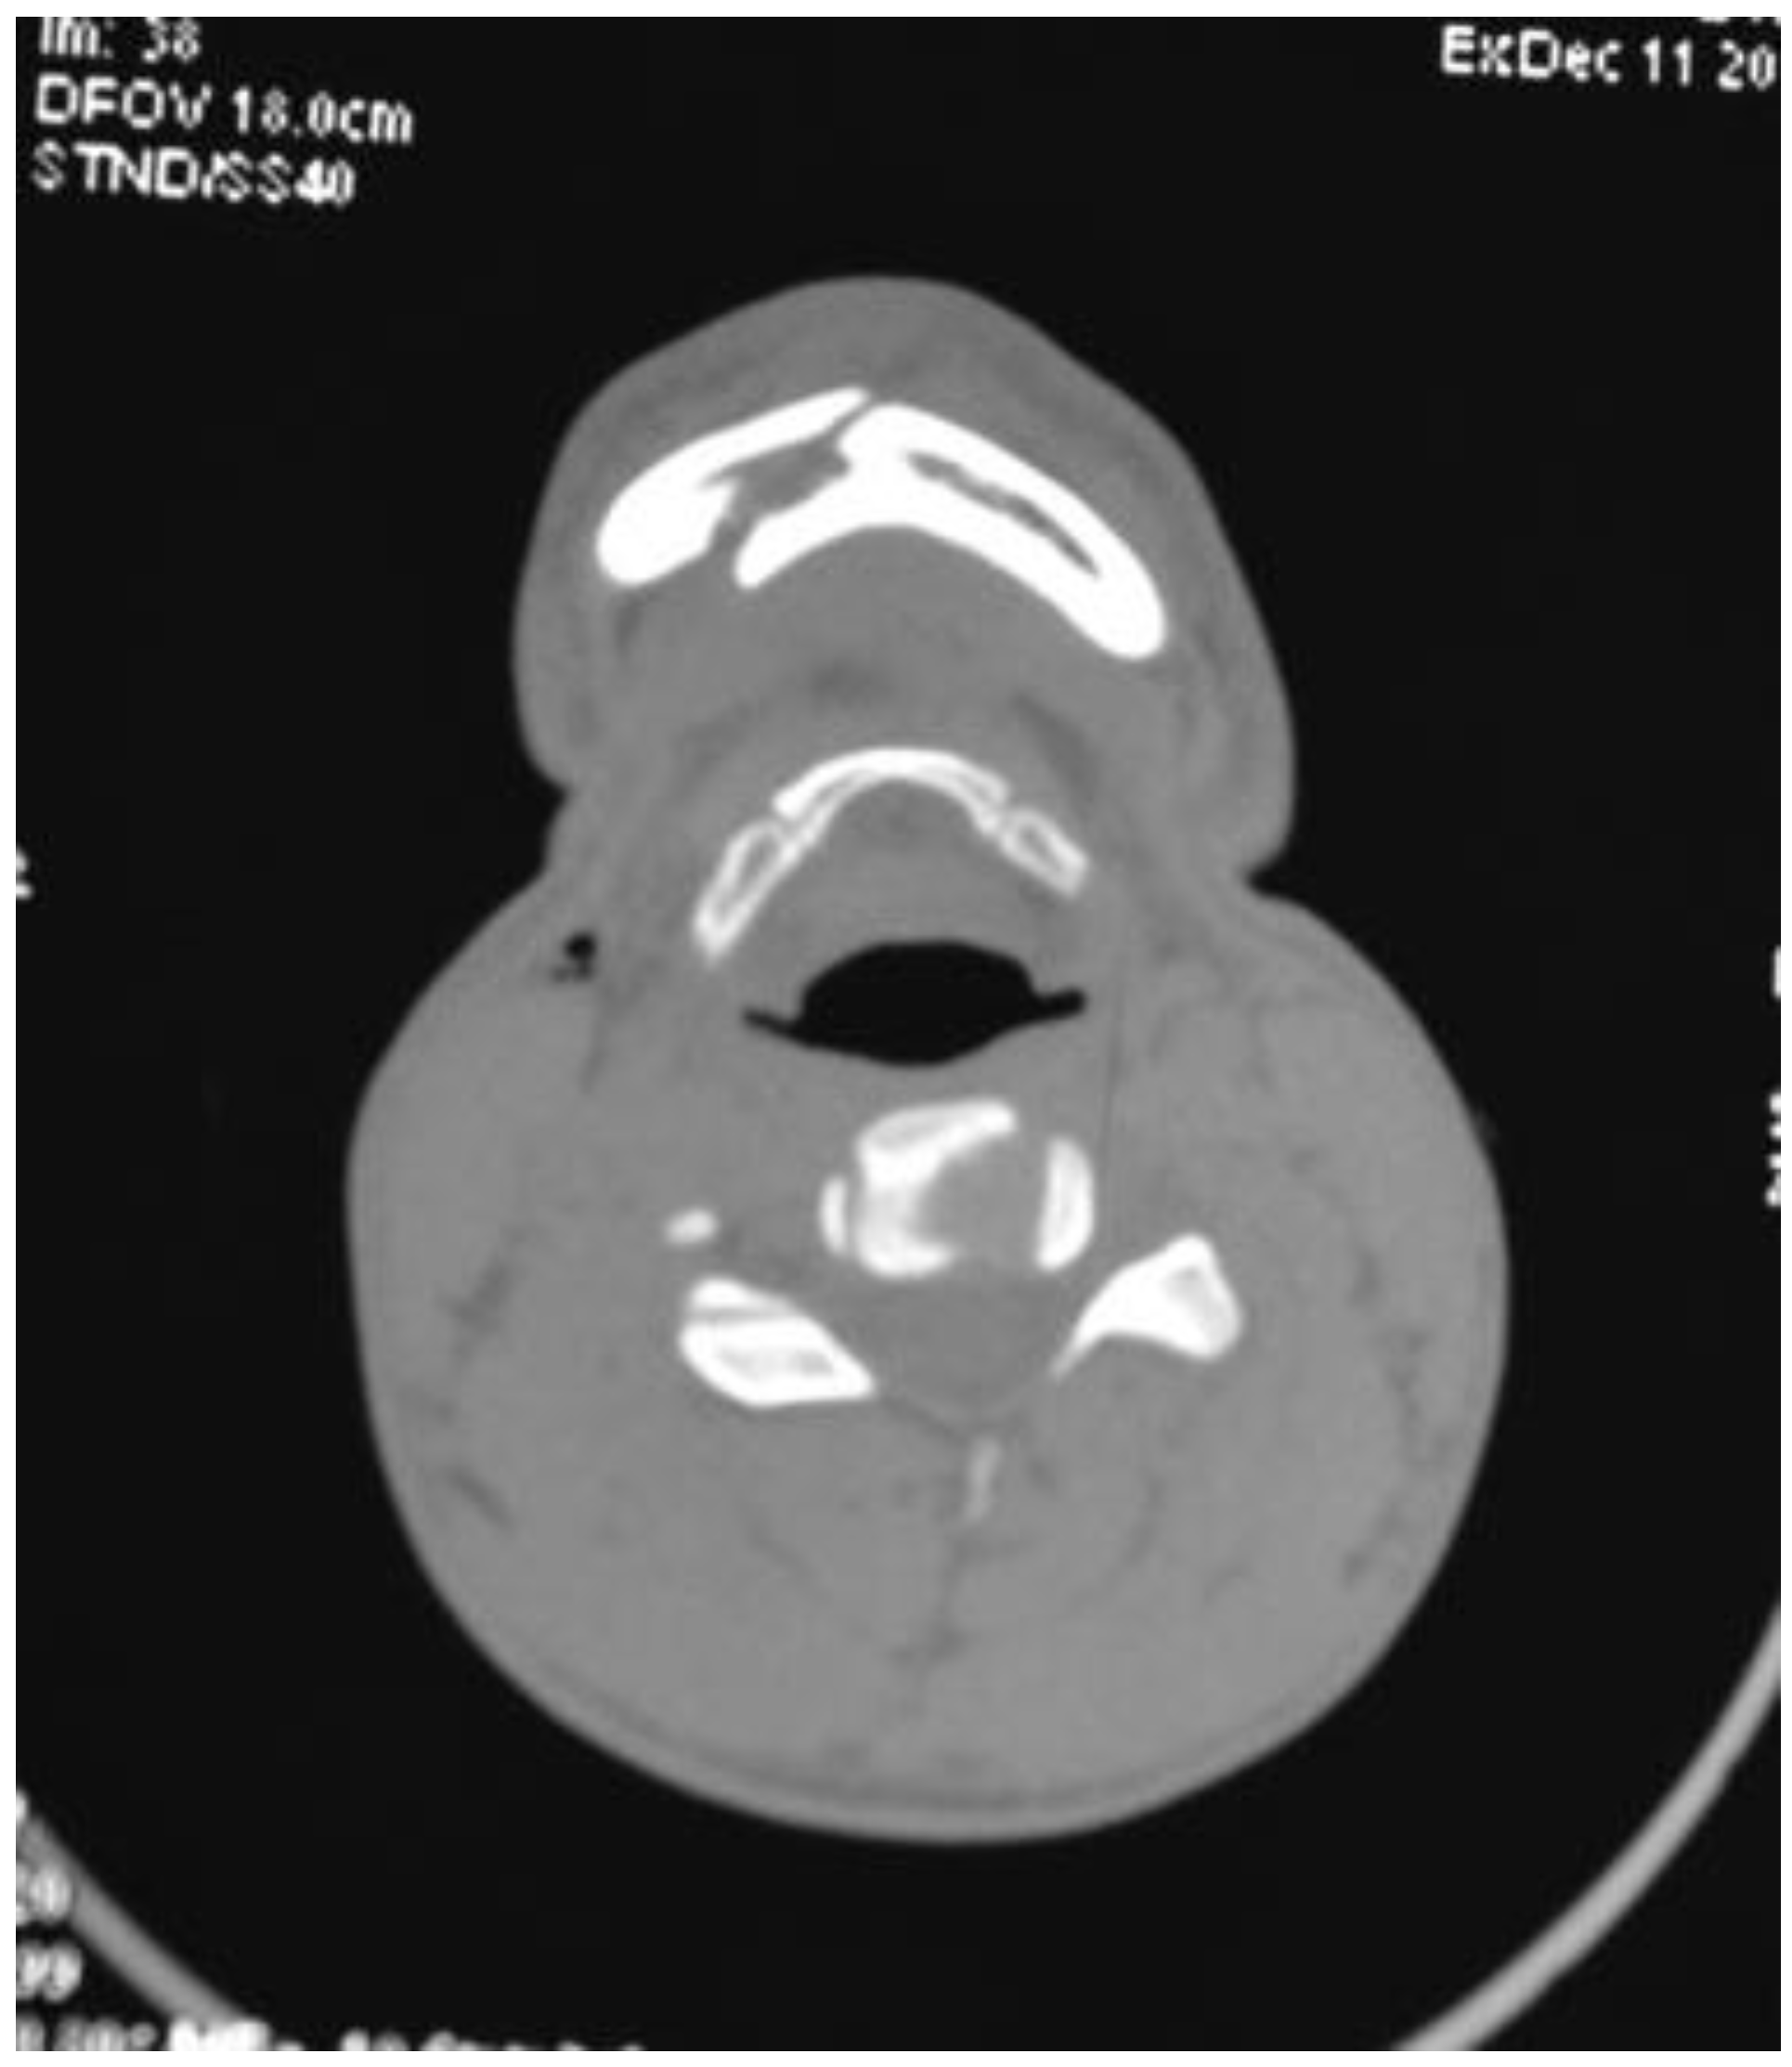

Six out of seven patients showed good anatomical reduction on postoperative CT scans (Figure 6, Figure 7, Figure 8 and Figure 9) and orthopan-tomograph (Figure 10, Figure 11, Figure 12 and Figure 13). On regular follow-up at 3 weeks, 3 months, and 6 months, and 1 year, no evidence of wound dehiscence, discrepancy in occlusion, or lower border malalignment was seen (Figure 14).

Figure 9. Case 2: Postoperative CT scan of axial section showing interforaminal mandible fracture reduced and fixed with a headless compression screw.